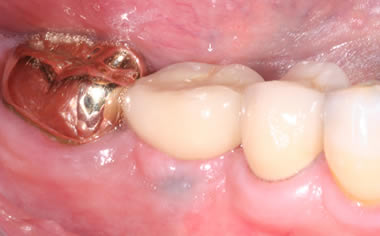

More back teeth replaced by dental implants

Case Three (2 images)

Case Four (4 images)

Case Five (4 images)

Case Six (8 images)

Case Seven (4 images)